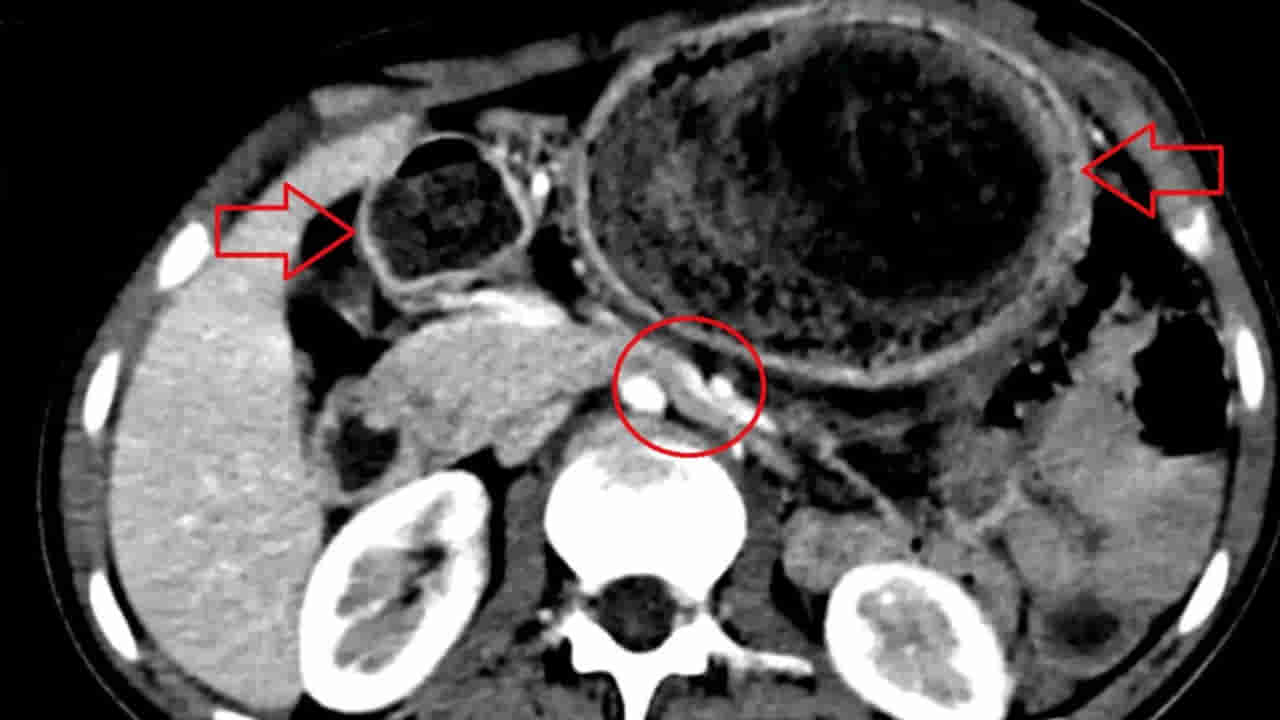

ఓ టీనేజర్ కడుపు నుంచి 4 పౌండ్ల బరువున్న భారీ వెంట్రుకల ముద్దను తొలగించారు డాక్టర్లు. ఆమె చిన్ననాటి నుంచి ట్రైకోటిల్లోమానియా అనే వ్యాధితో బాధపడుతోందని చెప్పారు. ఈ జబ్బు ఉన్నవారు జుట్టును తరచూ నమలడం, తినడం లాంటివి చేస్తారని చెప్పారు. దీని ఫలితంగానే ఆమె కడుపులో వెంట్రుకల ముద్ద ఏర్పడిందని తెలిపారు. CT-స్కాన్లో డాక్టర్లు ఈ హెయిర్బాల్ గుర్తించేసరికి.. సదరు యువతికి మానసిక చికిత్స పూర్తయిందట. ఈ వ్యాధి కారణంగా ఆమెకు తరచూ బరువు తగ్గడం, తీవ్రమైన కడుపు నొప్పి లాంటి లక్షణాలు వచ్చాయట.

గడిచిన ఆరు వారాల నుంచి తీవ్రమైన పొత్తికడుపు నొప్పితో ఆ 19 ఏళ్ల యువతి ఆస్పత్రిలో జాయిన్ అయింది. నొప్పి ఒక వారం పాటు కొనసాగగా.. రెండు నెలల పాటు ఆహారం తీసుకున్న వెంటనే పదేపదే వాంతులు రావడంతో పాటు, తేలికపాటి అనోరెక్సియా కూడా వచ్చేదట. అల్ట్రాసౌండ్, CT స్కాన్లో ఆ హెయిర్ బాల్ పరిమాణం డాక్టర్లకు స్పష్టంగా తేలింది. సుమారు రెండు గంటల పాటు శస్త్రచికిత్స నిర్వహించి కడుపులో 10 సెం.మీ, 4 పౌండ్ల హెయిర్ బాల్ తొలగించారు. ఈ ఆపరేషన్ అనంతరం.. యువతి పలు ఫ్లూయిడ్స్ ఎక్కించి.. ఆ తర్వాత డిశ్చార్జ్ చేశారు. కాగా, మూడు నెలల పాటు ఫాలో-అప్ తర్వాత సదరు యువతి పూర్తిగా కోలుకుంది.